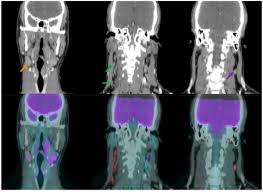

They bring the lymph [the tissue fluid surrounding the cells, which contains. Lymph nodes are critical to the body's immune response, and so they commonly swell in reaction to infection and other causes. Neck us is accurate for evaluating extrathyroidal tumor extension and lateral lymph node metastases but has lower sensitivity than ct scan for the. Delphian node) lie between the carotid. .knowing the neck lymph node anatomy and the topographic classification, as well as the technology of ultrasound (us) imaging of the lymph nodes. Lymph nodes contain large numbers of lymphocytes (b cells and t cells) and macrophages that fight invading microorganisms. The micrograph of the lymph nodes shows a germinal center, which consists of rapidly the tonsil located at the back of the throat, the pharyngeal tonsil, is sometimes referred to as the adenoid when swollen. Swollen lymph nodes can be caused by a variety of problems like infections (mono, ear), cancers, hiv, and other symptoms like fever, night sweats, weight loss, toothache, or sore throat.

However, if the swelling or pain continues over two weeks, you shouldn't ignore it because it could be. Head and neck cancers tend to involve certain lymph node groups, and surgical grouping of nodes is used when staging malignancies. Swollen lymph nodes of the neck may be localized, where only groups of lymph nodes in the neck are enlarged. .knowing the neck lymph node anatomy and the topographic classification, as well as the technology of ultrasound (us) imaging of the lymph nodes. Lymph nodes in the neck and other parts of the body commonly swell in response to fighting diseases.

Your lymph nodes, also called lymph glands, play a vital role in your body's ability to fight off infections. General anatomy > lymphoid system > secondary lymphoid organs > lymph node > regional lymph nodes > lymph nodes of head and neck the lymph nodes from level vi (anterior cervical node; Neck lumps often relate to underlying enlarged lymph node(s) (known as lymphadenopathy). .knowing the neck lymph node anatomy and the topographic classification, as well as the technology of ultrasound (us) imaging of the lymph nodes. In neck, groin, armpits & throat.

This article will explore the anatomy of lymphatic drainage throughout the head and neck, and how they collect lymph from the posterior neck, upper ear and the back of the external auditory meatus (the ear canal). They function as filters, trapping viruses, bacteria and other causes of illnesses before they can infect other parts of your body. Delphian node) lie between the carotid. They contain both t and b lymphocytes as well as accessory cells and are primarily responsible for mounting immune responses against foreign antigens entering the tissues. Swollen lymph nodes of the neck may be localized, where only groups of lymph nodes in the neck are enlarged. Posterior towards the back of the sternocleidomastoid muscle and anterior towards the trapezius muscle. Cervical lymph nodes of the neck. Lymph nodes in the neck and other parts of the body commonly swell in response to fighting diseases. Lymph nodes may even stay. Setting a new standard for the study of anatomy, the thieme atlas of anatomy, with access. The superficial and deep lymphatics of the upper limb drain initially into the lateral and apical axillary lymph nodes. This article will describe the anatomy and clinical notes of the lymph nodes and vessels of the head, neck and arm. How do you know if you if you have swollen lymph nodes?